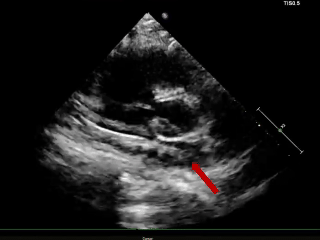

术后3个月随访

超声报告:(1)房间隔封堵器位置正常,各瓣叶形态活动未见异常,右心比例稍大,左房室腔不大,心包腔内未见液性暗区; (2)多普勒检查:房水平未见残余分流;心功能:室壁运动协调,未见节段性异常;(3)先天性心脏病房间隔缺损封堵术后未见残余分流。